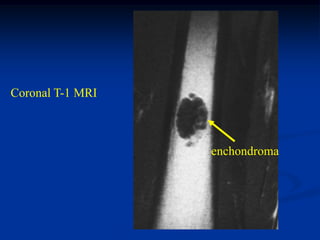

Coronal T-1 MRI